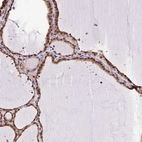

Immunohistochemical staining of human thyroid gland shows strong nuclear positivity in glandular cells.